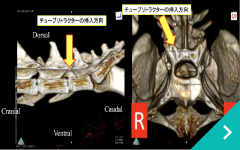

経皮的レーザー椎間板減圧術(PLDD)

経皮的レーザー

椎間板減圧術(PLDD)